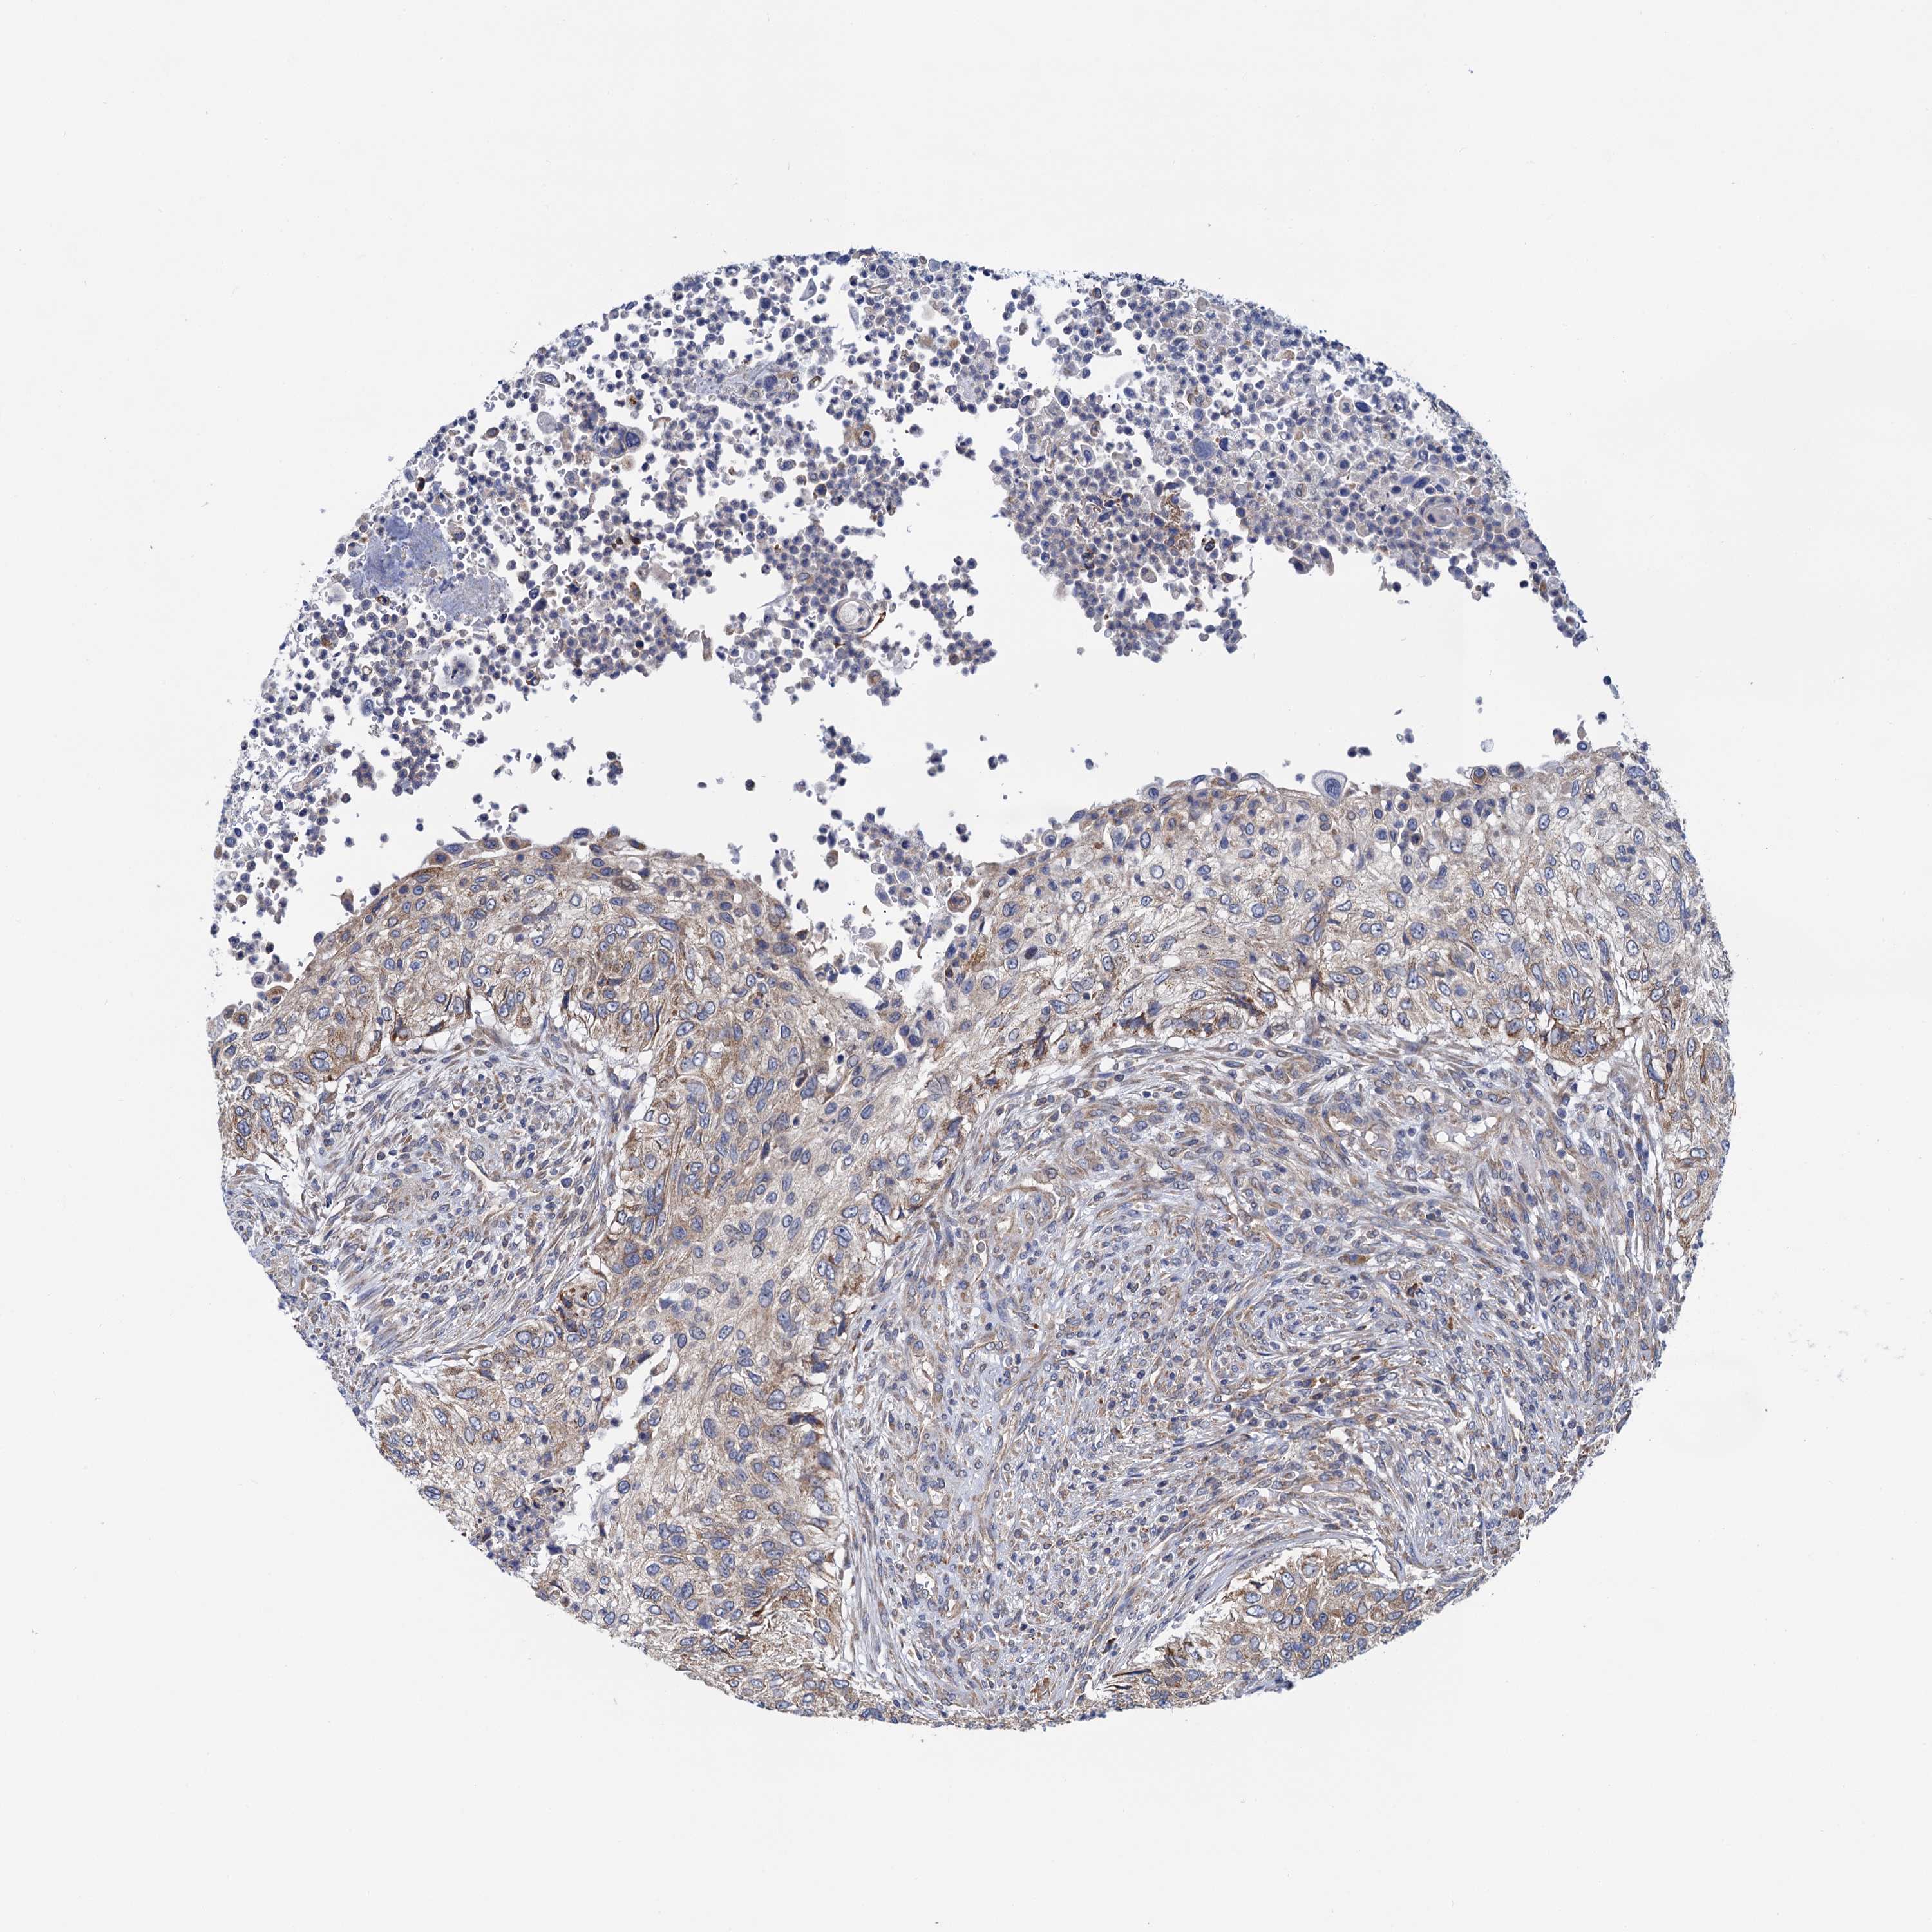

UROTHELIAL CANCER - Protein expressioni

A mouse-over function shows sample information and annotation data. Click on an image to view it in a full screen mode. Samples can be filtered based on level of antibody staining by selecting one or several of the following categories: high, medium, low and not detected. The assay and annotation is described here.

Antibody stainingi

Antibody staining in the annotated cell types in the current human tissue is reported as not detected, low, medium, or high, based on conventional immunohistochemistry profiling in selected tissues. This score is based on the combination of the staining intensity and fraction of stained cells.

Each image is clickable and will lead to virtual microscopy that enables deeper exploration of all samples and also displays staining intensity scores, fraction scores and subcellular localization as well as patient and tissue information for each sample.

Antibody HPA040744

Antibody HPA042032

Staining

High

Medium

Low

Not detected

Intensity

Strong

Moderate

Weak

Negative

Quantity

>75%

75%-25%

<25%

None

Location

Nuclear

Cytoplasmic/membranous

Cytoplasmic/membranous,nuclear

Urothelial carcinoma, Low grade